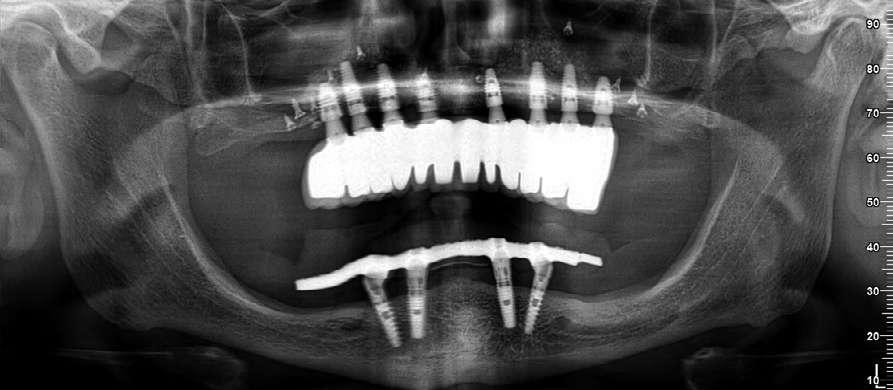

Figuras 3-6. Imágenes de un caso de prótesis atornillada en molar unitario inferior. Vemos el estado de los tejidos blandos gingivales tras la segunda fase y colocación del transepitelial unitario y la radiografía. En las imágenes inferiores (5 y 6) observamos el caso a los 4 años y 10 años de seguimiento, con estabilidad completa de los tejidos óseos peri-implantarios.

Figuras 7-10. En las dos imágenes superiores (7 y 8) observamos la realización de la prótesis cementada mediante un bioplilar fresado a la altura gingival con la radiografía antes del cementado de la corona. En las imágenes inferiores (9 y 10) vemos la prótesis a los 7 años de seguimiento y a los 9 años transformada en una prótesis atornillada al perderse la pieza anterior al implante y realizarse un puente con el nuevo implante. En este caso, el nivel óseo permanece estable con el paso del tiempo.